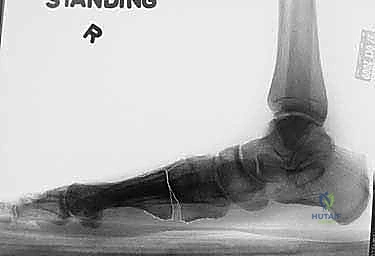

2. التصوير الشعاعي المتقدم

- الأشعة السينية مع تحمل الوزن (Weight-bearing X-rays): صور من الأمام، الجانب، والزوايا المائلة لتقييم زوايا العظام تحت تأثير وزن الجسم.

- الأشعة المقطعية (CT Scan): في الحالات المعقدة، يستخدم الدكتور هطيف الأشعة المقطعية ثلاثية الأبعاد لتقييم التئام العظام السابق، ومواقع المسامير القديمة، ودرجة خشونة المفاصل بدقة متناهية.